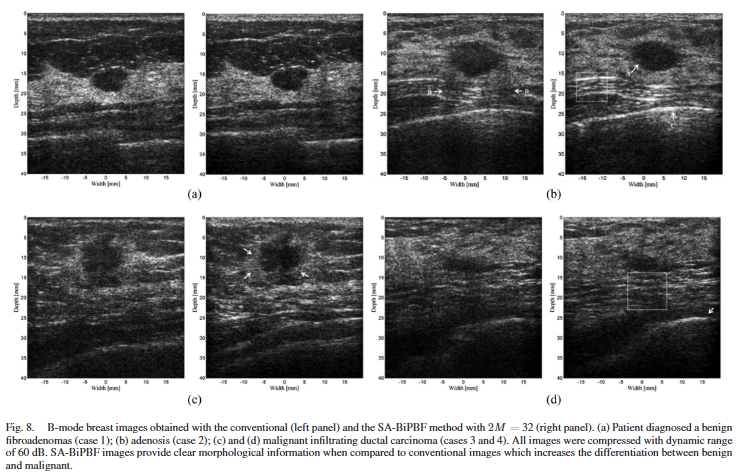

In vivo 실험은 유방 병변 환자 10명(양성 5, 악성 5) 을 대상으로 수행되었다. 모든 병변은 조직검사 또는 수술 결과로 확진되었으며, 각 환자에 대해 conventional 영상과 SA-BiPBF 영상이 순차적으로 획득되었다. SA-BiPBF에서는 2M = 32 설정이 사용되었다.

정량 평가 결과, SA-BiPBF는 평균적으로 CNR과 SNR 모두에서 conventional 방식보다 높은 값을 보였다. 특히 SNR 개선은 통계적으로 유의미한 수준이었으나, CNR 개선은 통계적 유의성에 도달하지는 못했다(Table 2.).

F. 방사선과 전문의 블라인드 평가

두 명의 방사선과 전문의는 영상 획득 방식에 대한 정보 없이 무작위로 배열된 영상 쌍을 비교 평가하였다. 평가 기준은 병변의 conspicuity, margin sharpness, contrast, 심부 구조 해상도였다. 전반적으로 SA-BiPBF 영상은 병변 경계가 더 명확하고 심부 구조의 해상도가 향상되어 임상적 판독에 유리하다는 평가를 받았다.

다만 모든 변화가 긍정적으로 해석되지는 않았다. 예를 들어, 강한 반사체(뼈) 인근에서는 반사 아티팩트가 오히려 강조되거나, 일부 경우에서는 기존에 악성 지표로 활용되던 edge shadowing 아티팩트가 감소하여 판독 기준에 혼선을 줄 가능성도 지적되었다. BI-RADS 및 ROC 분석에서도 SA-BiPBF가 다소 높은 AUC를 보였으나 표본 수가 제한적이어서 통계적 유의성은 확보되지 않았다.